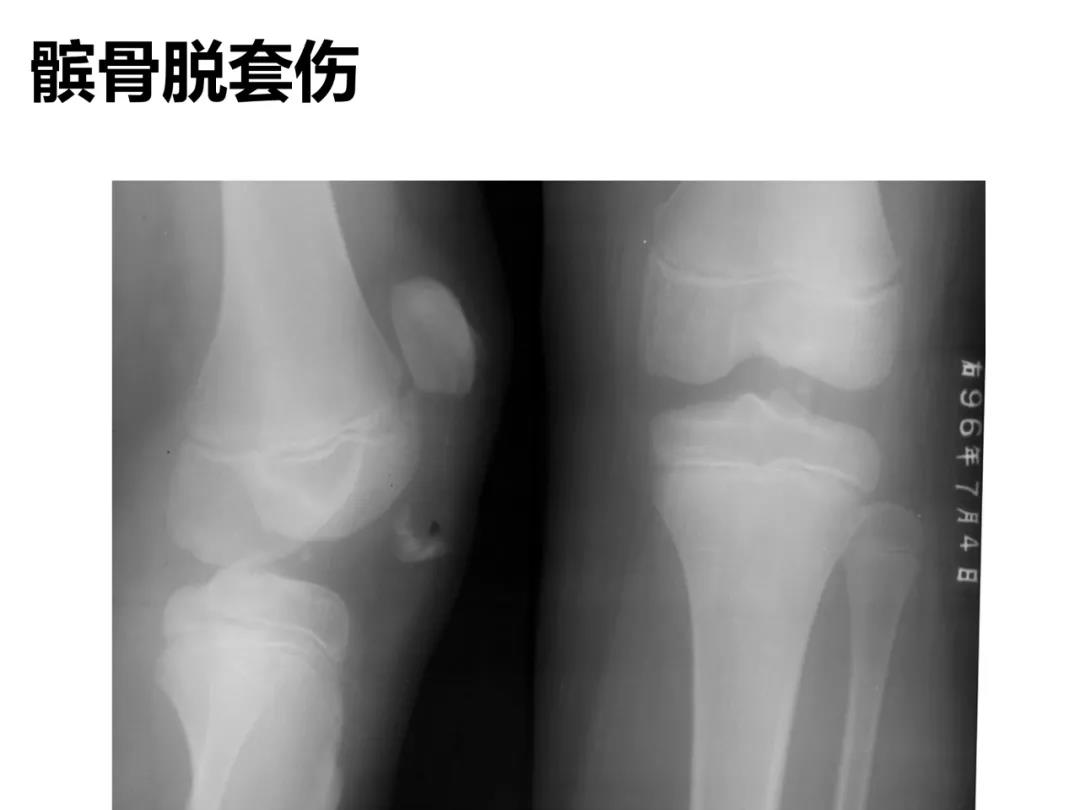

小儿骨科X线片汇总,临床读片宝典!